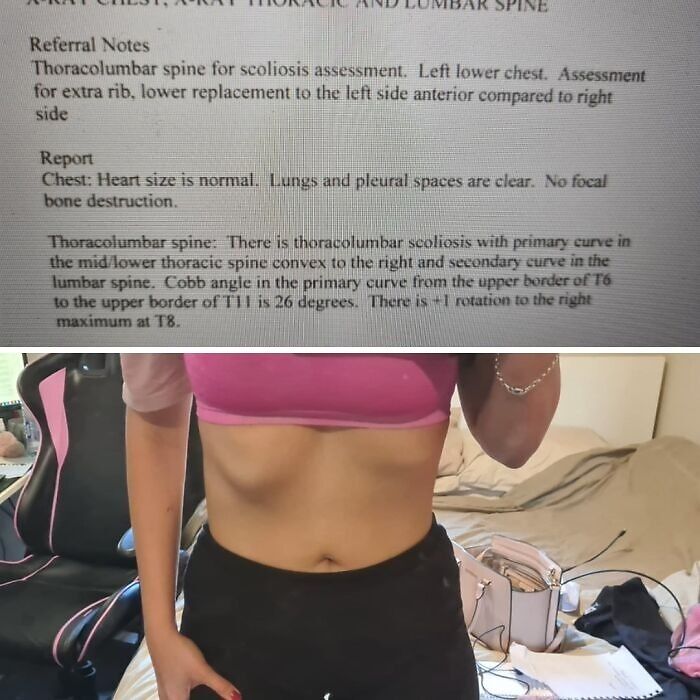

Update: Reddit Called My Scoliosis With My Ribs! Went And Got An Xray And The Doctor Confirmed. Ive Got Physiotherapy Tomorrow. Thanks Reddit :)

My ribs look exactly like that! I've had back issues my entire adult life.